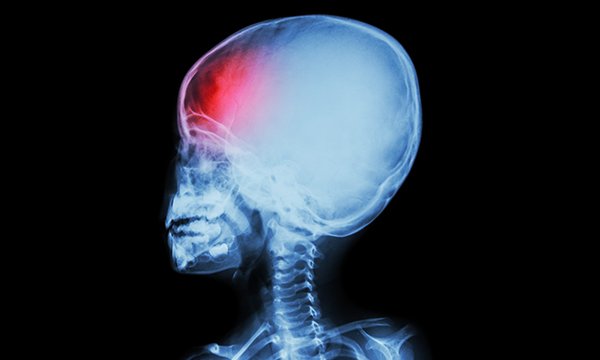

Neurological observations in infants, children and young people: part two

Neurological observations in infants, children and young people: part one